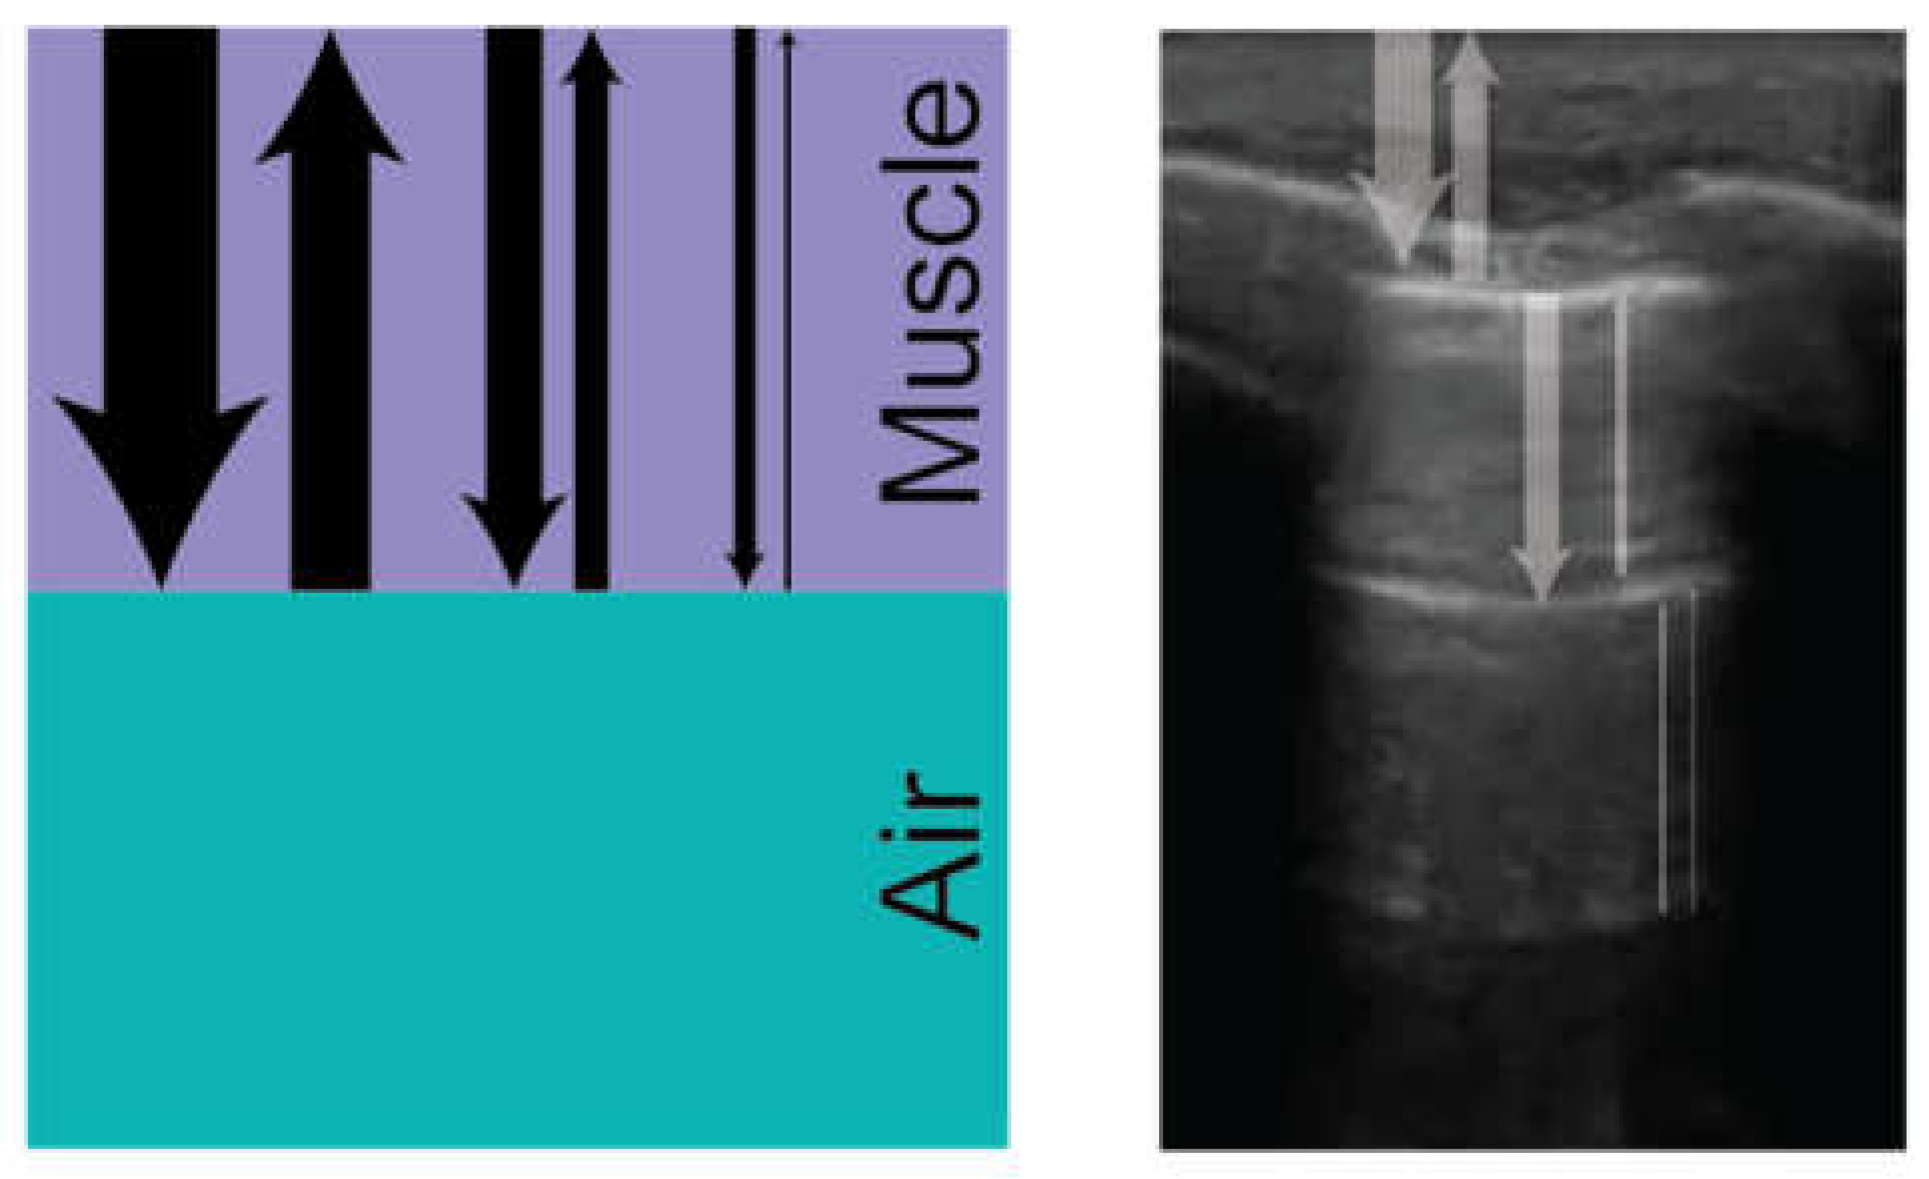

Ultrasonography is based on the passage of sound waves through tissue with subsequent reflection of waves back to the emitting transducer, which converts the sound into electrical signals and creates a two-dimensional image [4,13,14]. The physical properties of the medium through which sound waves pass and the interfaces between different types of tissues dictate the details of the image. Dense tissues reflect more sound back to the transducer, leading to more received signal and a more “hyperechoic” or “bright” area on the screen, while less dense tissues reflect less sound and are interpreted by the machine as “hypoechoic” or “dark.” Dense tissues also have higher impedance and generally transmit sound waves faster, while less dense tissues have lower impedance and transmit sound waves slower [14]. Interfaces between tissues that transmit sound at significantly different speeds cause marked reflection and refraction of ultrasound beams, as governed by Snell’s law (Sin( θ   r)÷ Sin( θ   i) =C1/C2) (Figure 2) [13]. This interplay between sound waves and lung tissue creates artifacts in both normal lungs and lung parenchyma in various states of pathology. For instance, within normally inflated lungs, the sound initially passes into soft tissue (speed 1540m/s) before meeting an interface with air-filled alveoli (speed 330m/s) leading to most of the sound being reflected to the transducer. This results in a bright hyperechoic line overlaying a dark black shadow representing the pleural line and lung parenchyma below.

Figure 2. The variation in ultrasound wave propagation through different tissues, showing minimal refraction between muscle (1580 m/s) and fat (1450 m/s) but significant reflection and refraction at the muscle-air interface (330 m/s). The impedance mismatch with air results in poor ultrasound image quality due to wave reflection.